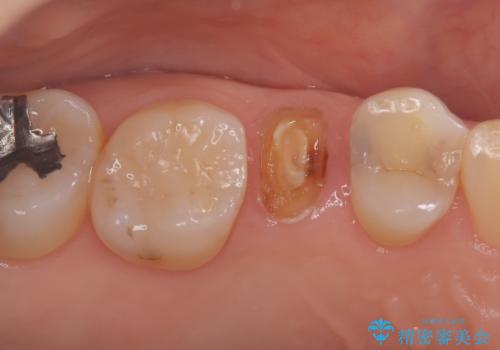

- 患者様は「歯が取れたこと」を主訴に来院されました。

診査の結果、土台ごと脱離しており、歯質の残存量も少ない状態でした。

患者様は歯の保存を強く希望されたため、保存可能な範囲で丁寧に形成を行い、フェルール(歯冠縁下の歯質保持)を確保することを優先しました。